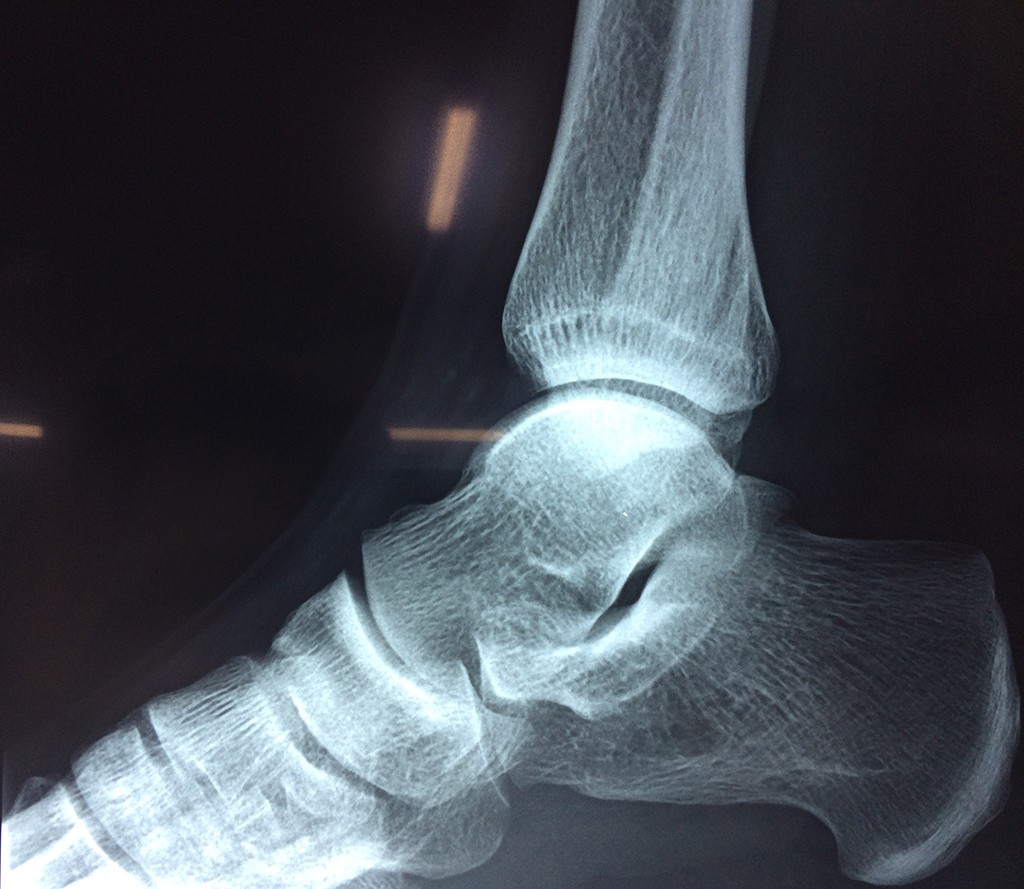

Una fractura de tobillo es la rotura de uno o más de los huesos del tobillo. Estas fracturas pueden ser:

Cuando se necesita cirugía, es probable que esta implique el uso de clavijas de metal, tornillos o placas para sostener los huesos en su lugar mientras la fractura se consolida. Los elementos de soporte pueden ser temporales o permanentes.